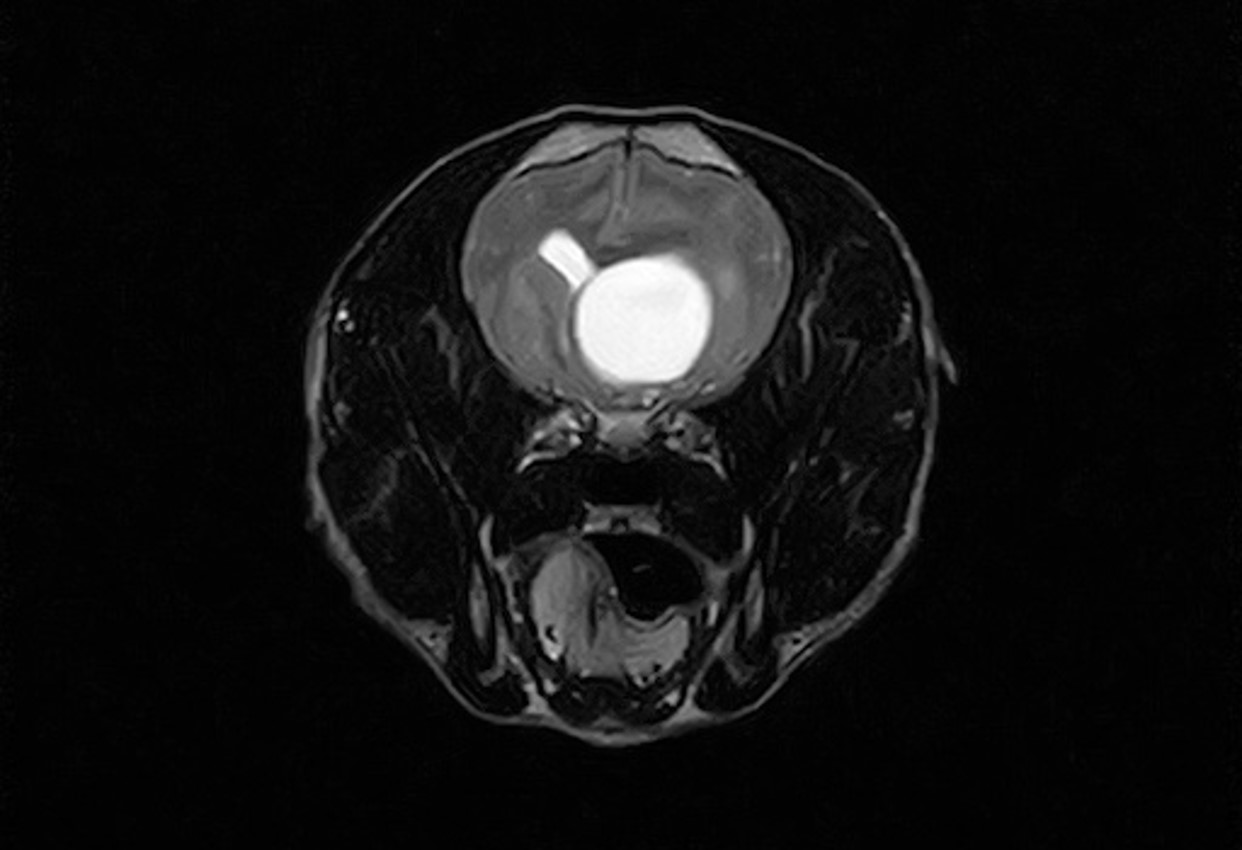

犬の脊髄腫瘍に対し椎弓切除術を実施し、病理検査で悪性末梢神経鞘腫瘍と診断された1例の画像

2026.02.04

犬の脊髄腫瘍に対し椎弓切除術を実施し、病理検査で悪性末梢神経鞘腫瘍と診断された1例

• 麻酔管理部門

• 脳神経部門

• 画像診断部門

• 田村 勝利